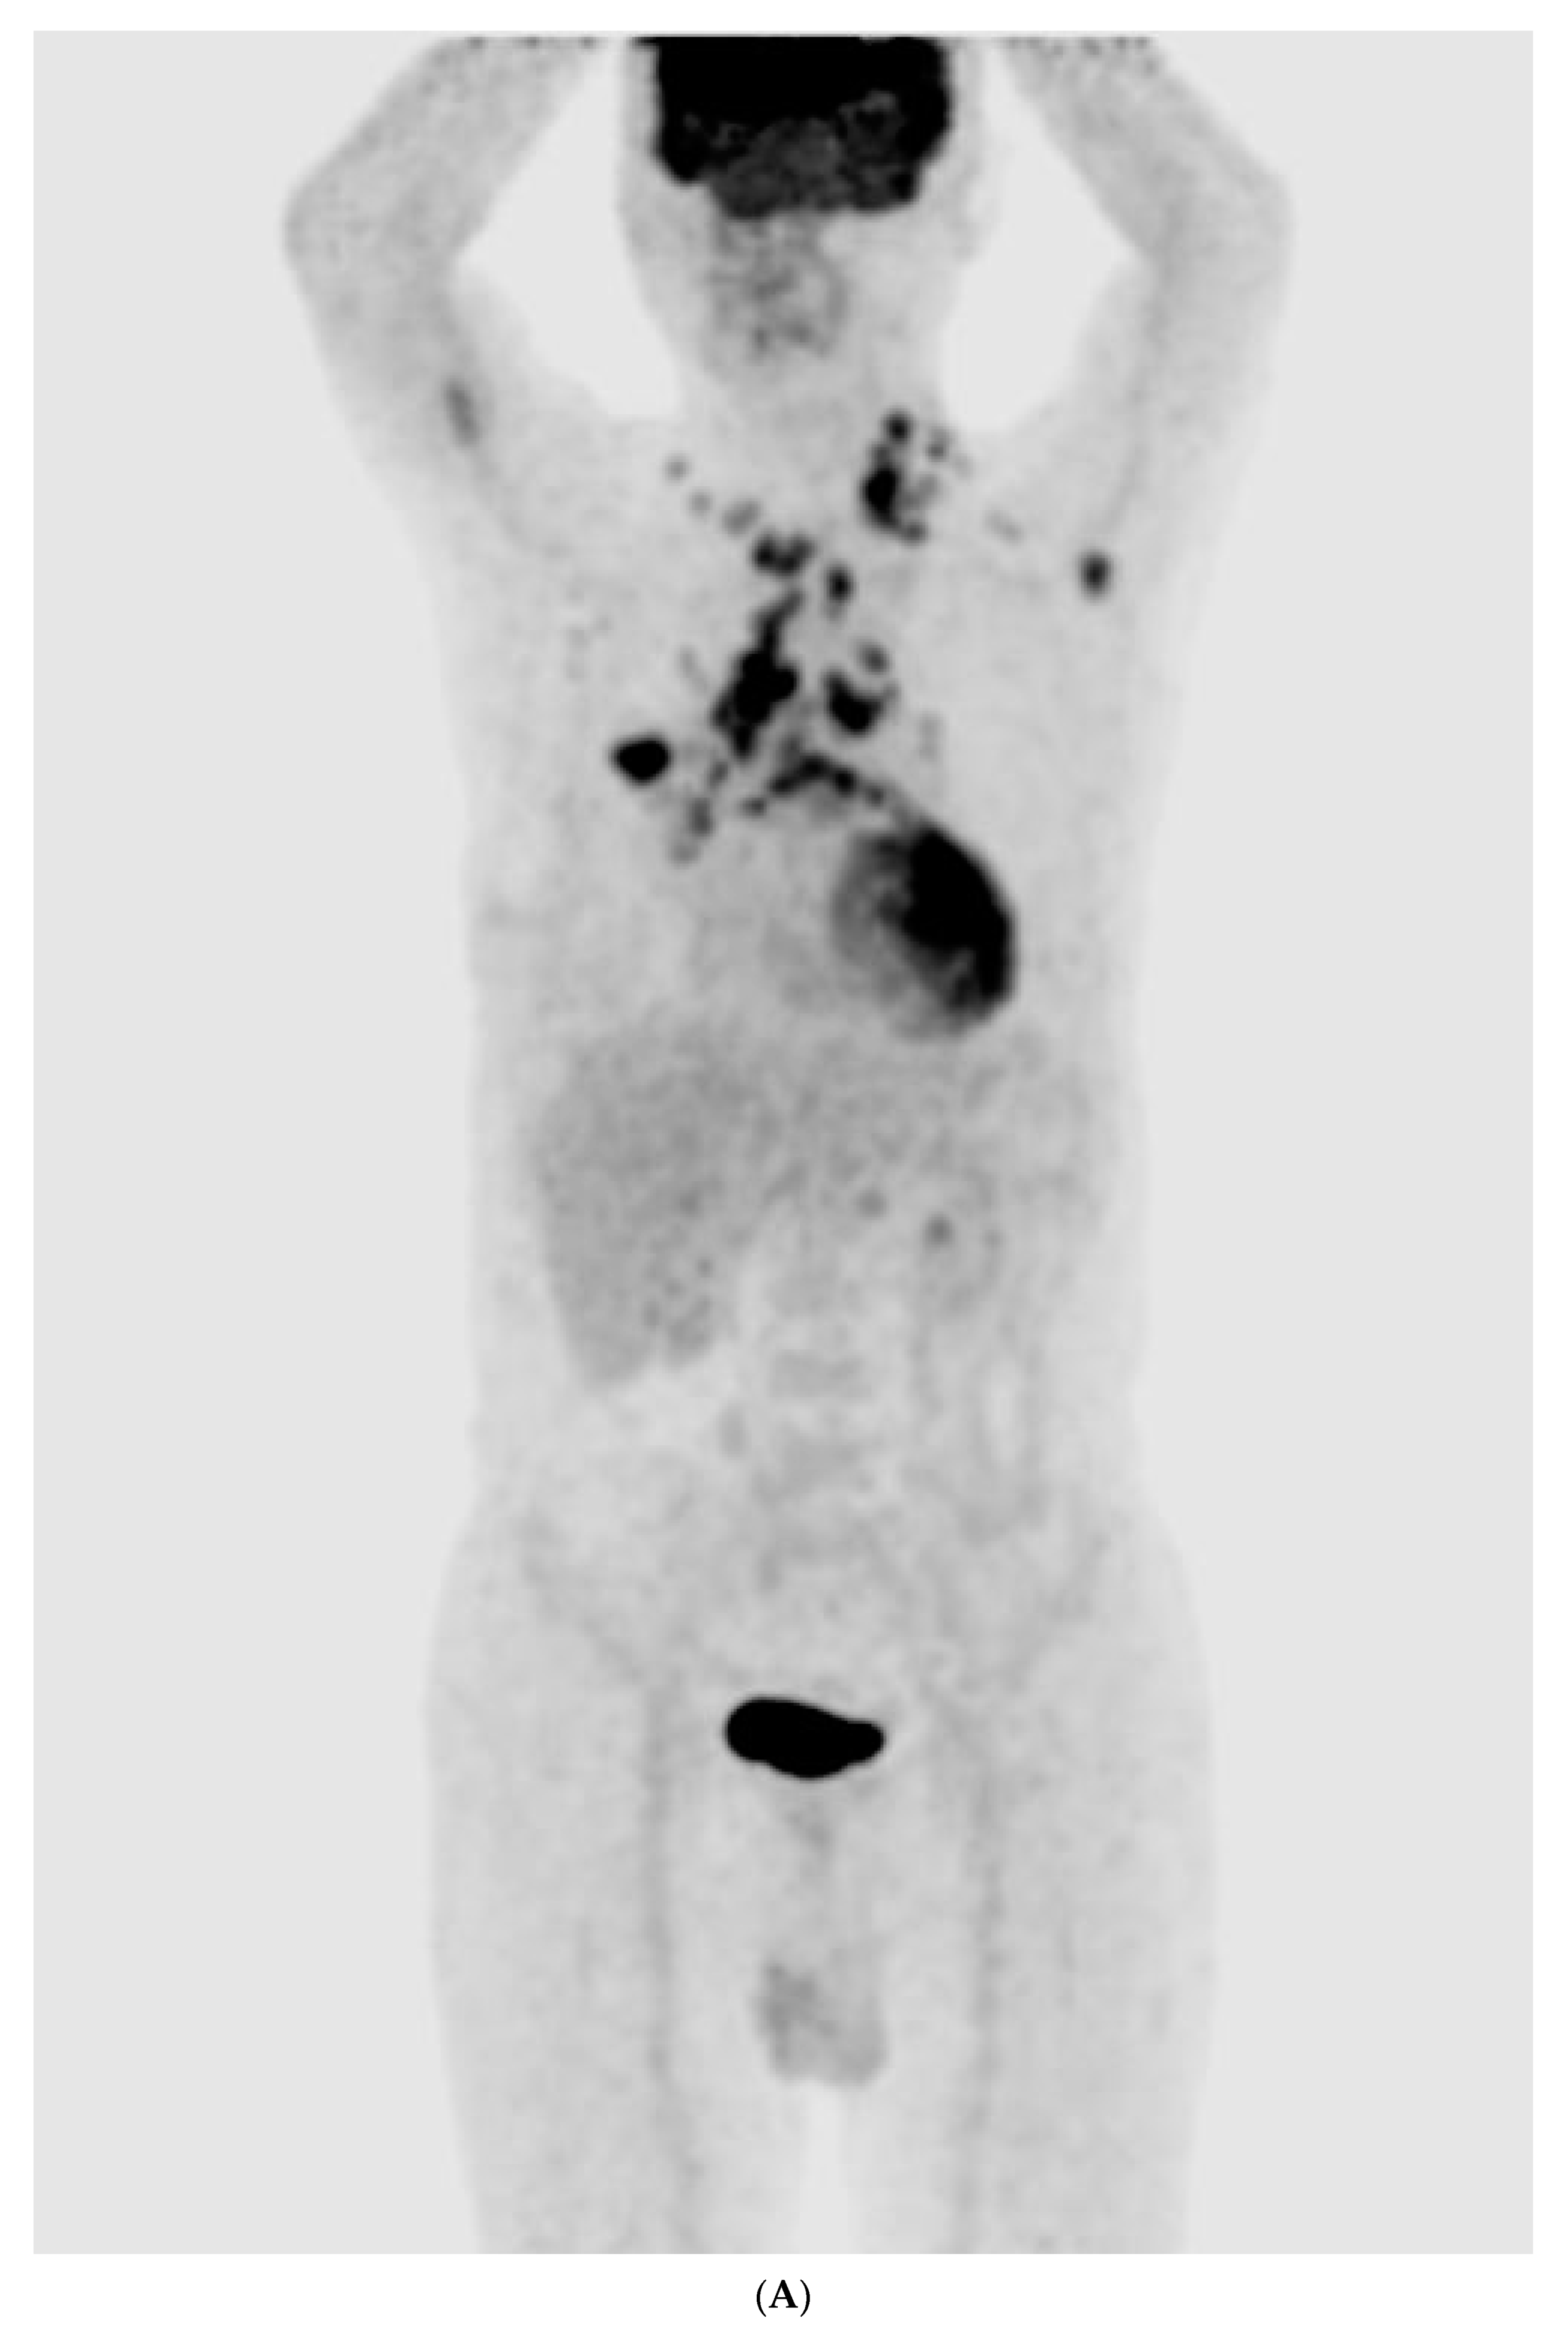

2. Case Report